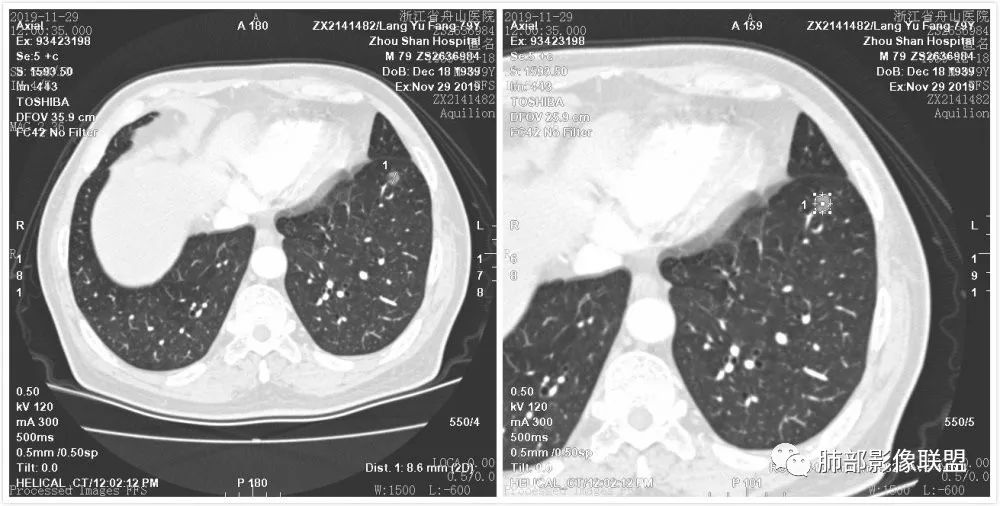

病例3

血管从凹陷处进入

边界清晰GGN,内血管走形自然、稍增粗,考虑MIA 医学百科网 | YxBaike.Com

左肺下叶前内基底段磨玻璃小结节,边界清,有分叶,直径8.5mm,CT值-450,内见增粗血管,VR表面有收缩,考虑浸润性病变,MIA 医学百科网 | YxBaike.Com

这个胸膜改变怎么解释?

牵拉凹陷,胸膜下积液

少量积液聚集

胸膜腔间本来有润滑液的,负压下可以局部吸引积聚

肿瘤侧胸膜牵拉明显,对侧叶胸膜只是被吸引过来一点,所以两层胸膜间有负压吸引微量液体积聚,不是浸润 医学百科网 | YxBaike.Com

病理诊断 LPA(贴壁庄生长为主浸润腺癌,非黏液性腺癌)

应该是比较轻的LPA 医学百科网 | YxBaike.Com